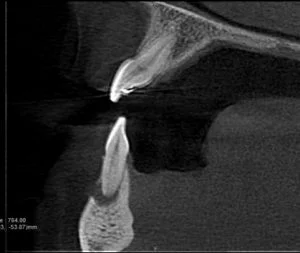

A CBCT was taken after a negative cold test indicated a necrotic tooth. When the CBCT was taken, we could clearly see that the abscess had completely perforated the labial bone at the apex of #24 and was close to doing so on #25.

As we investigated more deeply, we identified another critical piece of information that would affect our treatment plan: a second canal on #24.

Had I initiated treatment on this particular tooth and kept my access very conservative, there’s a chance I would have missed the other canal. Furthermore, had I started the treatment and then found the second canal after access into the chamber, I would have had to spend time determining the anatomy of both canals. For example, I would have had to determine if they had separate apicies.